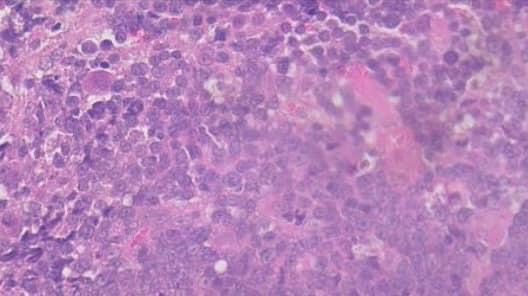

• 白血病 骨髓抑制 不再生性貧血 原發性淋巴瘤

白血病 骨髓抑制 不再生性貧血 原發性淋巴瘤

• 貓白血病及淋巴瘤

貓白血病及淋巴瘤